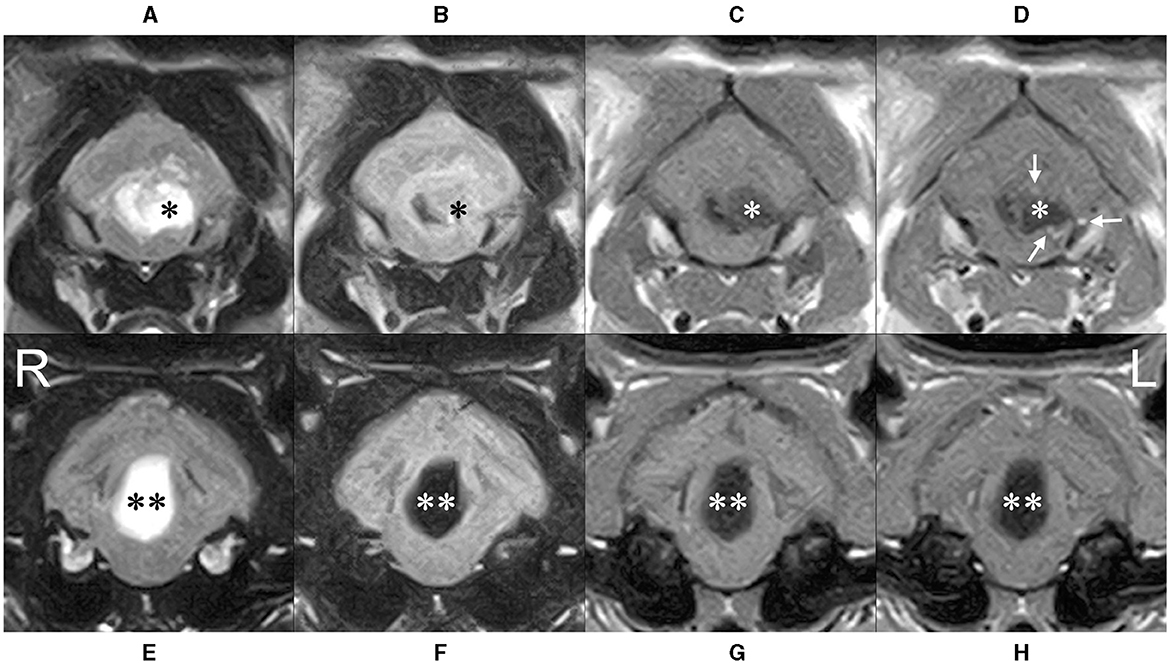

El paciente fue premedicado con midazolam (Dormicum, Maruishi Pharmaceutical Co., Osaka, Japón; 0,2 mg/kg IV) y anestesiado con propofol (PropoFlo28, Zoetis Japan, Tokio, Japón) inyectable para hacer efecto. Después de la intubación endotraqueal, se mantuvo la anestesia general con sevoflurano al 2% (SEVOFLO, Maruishi Pharmaceutical Co., Osaka, Japón). La resonancia magnética se realizó con 0,3T AIRIS Vento (Hitachi, Tokio, Japón) con planos sagital, transversal y dorsal en imágenes ponderadas en T2 (TR/TE = 4.000/100); planos transversales en imágenes ponderadas en T1 (TR/TE = 380/15); y la recuperación de inversión atenuada por fluidos (FLAIR; TR/TE = 9.000/100). También se realizaron planos sagital, transversal y dorsal de imágenes ponderadas en T1 después de la inyección intravenosa de gadolinio (OMNISCAN 32%, GE HealthCare Pharma Co., Tokio, Japón; 64 mg/kg IV). La resonancia magnética reveló una lesión de masa extraaxial en la médula dorsal y el cuarto ventrículo caudal, comprimiendo la médula ventralmente y el cerebelo dorsalmente (Figura 1). La masa era de alta intensidad en las imágenes ponderadas en T2 y FLAIR, de baja intensidad en las imágenes ponderadas en T1 (superior a la señal del líquido cefalorraquídeo) y se realzó en los márgenes en las imágenes ponderadas en T1 posteriores al contraste (Figura 2). El tercer ventrículo, los ventrículos laterales y el ventrículo olfatorio estaban agrandados, y los surcos estaban oscurecidos en su totalidad. A partir de estos hallazgos, sospechamos que el paciente presentaba una hidrocefalia obstructiva secundaria a una lesión masiva caudal al cuarto ventrículo. Los quistes epidermoides, los divertículos aracnoideos, los abscesos y las neoplasias (p. ej., meningioma, linfoma y ependimoma) fueron diagnósticos diferenciales de la masa (8-11). Se consideró necesario un examen histopatológico para el diagnóstico. Se encontró una segunda lesión quística entre el tectum y el cerebelo, dorsal a la cisterna cuadrigeminal. Esta lesión mostró el mismo patrón de señal que el líquido cefalorraquídeo: alta intensidad en las imágenes ponderadas en T2, baja intensidad en las imágenes ponderadas en T1 y en las imágenes FLAIR y sin realce de contraste. Se sospechó que esta lesión concurrente era un divertículo aracnoideo, pero el significado clínico de la lesión no estaba claro.

En nuestro caso, el quiste se representó en la resonancia magnética como un quiste ovalado bien definido junto al cuarto ventrículo. El interior del quiste mostró alta intensidad en las imágenes ponderadas en T2 y FLAIR, baja intensidad en las imágenes ponderadas en T1, y la pared del quiste se realzó ligeramente con el medio de contraste en un patrón similar a un anillo. Se ha reportado un patrón de señal similar en quistes epidermoides caninos, lo que sugiere que tales hallazgos de imágenes pueden ser comunes en gatos y perros (1, 4). Existe muy poca información a la hora de considerar el diagnóstico diferencial de las lesiones quísticas en el cuarto ventrículo en gatos, ya que hasta el momento solo se han descrito abscesos y divertículos aracnoideos (10). En los perros, los quistes dermoides, los quistes del plexo coroideo y los quistes ependimarios son otras lesiones quísticas en el cuarto ventrículo, y se pueden diferenciar de los quistes epidermoides mediante resonancia magnética (1, 4, 16, 17). En las imágenes T1W con contraste, los abscesos muestran una lesión en forma de anillo más gruesa que los quistes epidermoides y los quistes del plexo coroideo muestran un realce de contraste fuerte y homogéneo (10, 16). Los divertículos aracnoideos y los quistes ependimarios muestran baja intensidad en las imágenes FLAIR (1, 17). Los quistes dermoides son similares a los quistes epidermoides en el sentido de que contienen epitelio escamoso estratificado, pero se distinguen histológicamente por la presencia de órganos que forman los folículos pilosos, como el cabello, las glándulas sudoríparas y las glándulas sebáceas en los quistes dermoides. Es por eso que los quistes dermoides a menudo muestran una alta intensidad heterogénea en la RM ponderada en T1 debido a la presencia de lípidos, mientras que los quistes epidermoides a menudo muestran una intensidad baja (1, 4). Otras lesiones masivas, no necesariamente quísticas, que pueden ocurrir en el cuarto ventrículo en los gatos son tumores, incluidos el meningioma, el linfoma, el ependimoma y los tumores metastásicos (11, 18, 19). Estos tumores a menudo muestran un realce de contraste de moderado a fino (11, 20), mientras que los quistes epidermoides suelen mostrar un ligero realce de los anillos. Aunque el diagnóstico definitivo requiere una evaluación patológica, los hallazgos de la resonancia magnética en nuestro caso apoyan el diagnóstico de un quiste epidermoide y son comparables a los informes de otras especies.